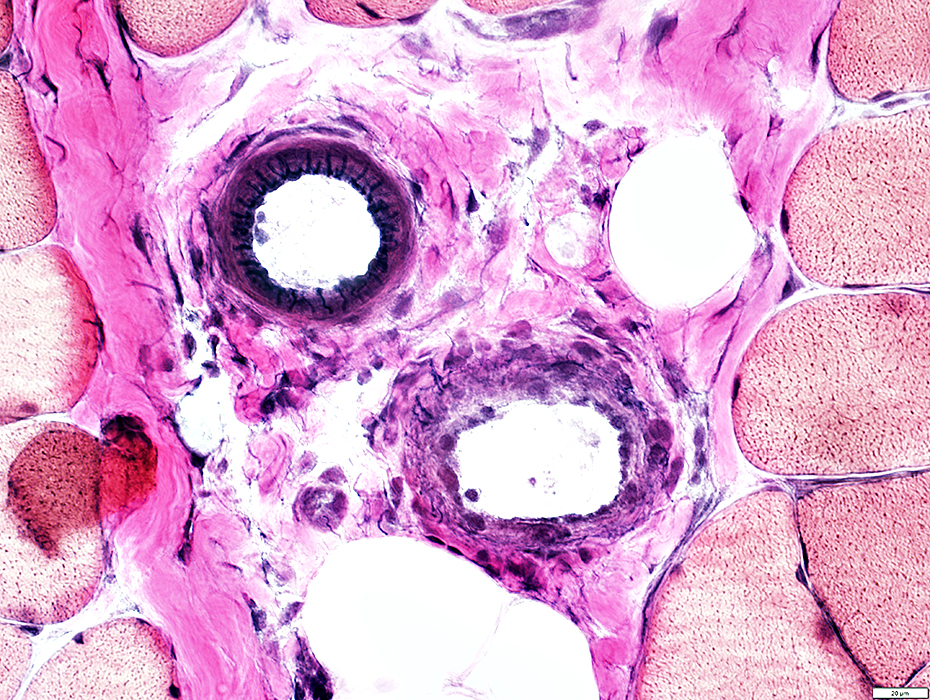

H&E stain

Muscle Fibers

Minimal damage

Sizes

Moderate Atrophy

Mild variation

Perimysial Vessel

Associated inflammation

Pale walls

Vessels

Perimysial Vessel Pathology: Associated Inflammation

Perivascular Inflammation

Vein Pathology

Walls: Pale

Walls: Pale; Absent fibrils

Arteries: Normal